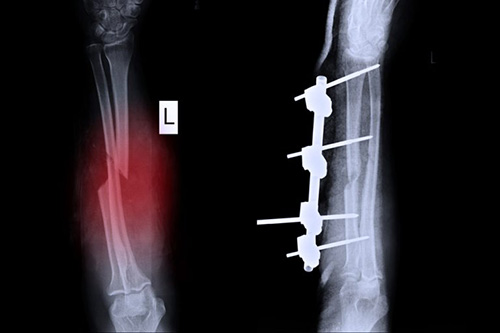

Internal splinting

Installs plates or screws to stabilize bone structure long‐term.